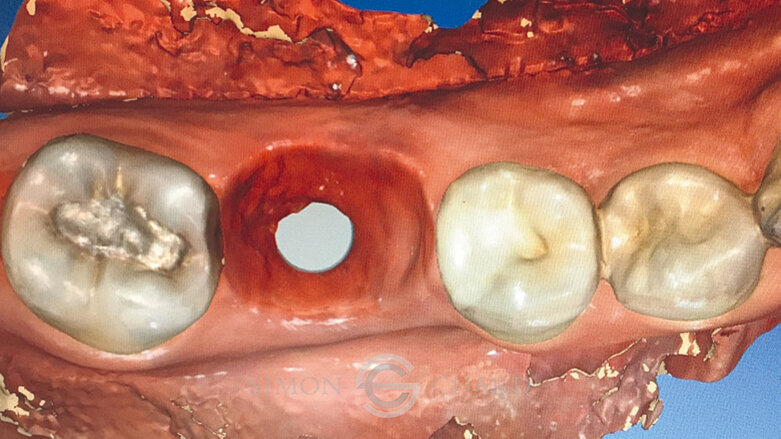

Obvykle při použití metod s analogy je právě detailní zachycení profilu měkké tkáně okolo implantátu komplikované a časově náročné. Nicméně, při použití digitálního intraorálního skenování (CEREC Omnicam) můžeme využít „skenu gingivální masky“ k přesné replikaci měkkých tkání a k modelaci emergence profile výsledné korunky (obr. 6).

Po sejmutí provizorní korunky byla na implantát dosazena TiBase se skenovacím tělískem tvořícím referenční bod pro sken implantátu.

Následně byl po oskenování protiskusu, preparace a skusového skenu vyhotoven digitální design korunky za využití individuální biogenerické funkce. V rámci této techniky software CERECu vyhodnotí ostatní zuby zachycené ve skenu a pokusí se vytvořit takový návrh korunky, který podle něj co nejvíce odpovídá původnímu, již chybějícímu zubu. Tento návrh je poté digitálně umístěn do e.max meso bločku. Tento bloček má v sobě již vytvořen předdefinovaný otvor, který slouží jako přístup k fixačnímu šroubu, stejně jako ústí, do kterého bude vlepena TiBase (obr. 12).